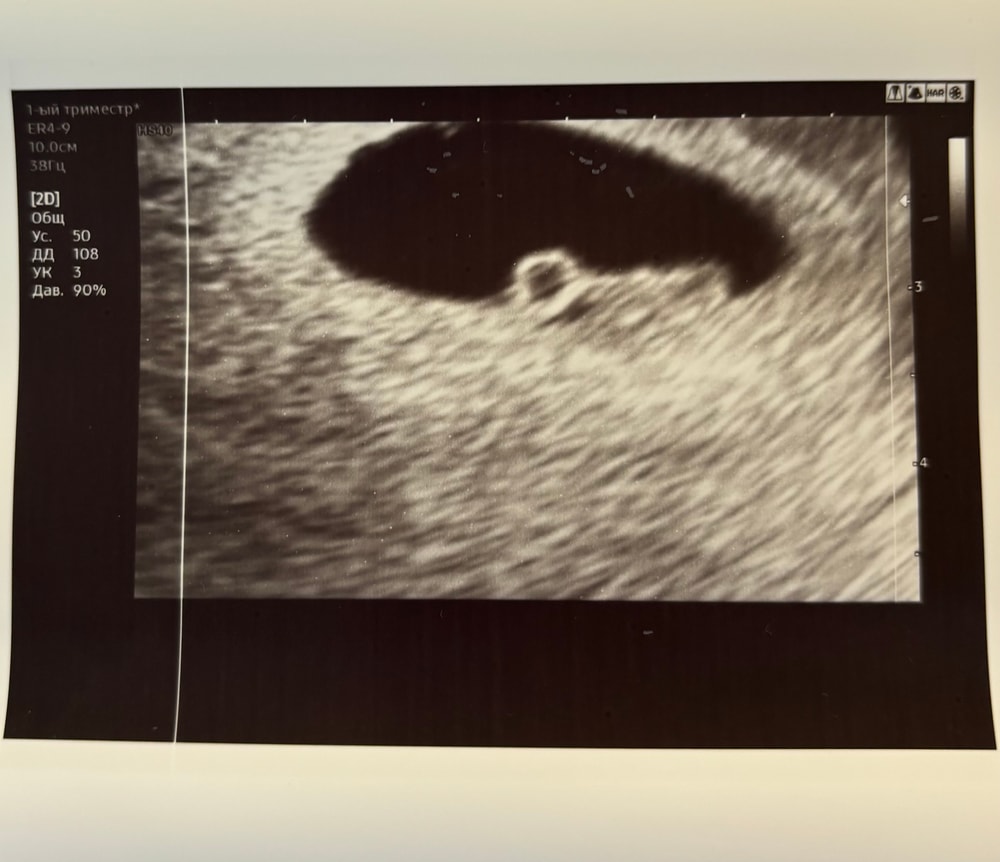

Всем привет🍀 Ходила на днях на повторное узи, все хорошо, малыш растёт. По месячным срок 6 недель и 4 дня в среду был , а по узи уже целых 7, врач сказала, что, вероятно, ранняя овуляция была. Дали послушать сердечко, эмоции, конечно, непередаваемые😅